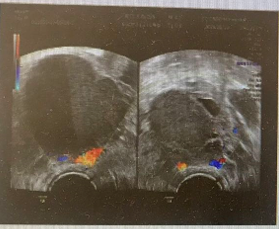

患者丁某,女,35岁,因“发现附件包块10年,经期延长4+年”于2022年1月24日入院 现病史:患者于10年前在外院体检时发现附件包块,自述大小约2+cm,患者无月经改变,无痛经等不适,嘱随访。4+年前无明显诱因出现月经经期延长,由原来5天延长至7-10+天,月经周期及经量无明显改变,患者曾于外院复查B超提示附件区包块无明显改变,遂继续随访。2+年前患者因“腹痛”于外院就诊,行后穹隆穿刺抽出咖啡色液体,考虑巧囊破裂,建议患者手术治疗,但患者拒绝,后经保守治疗腹痛缓解后出院。1+月前患者就诊于我院,复查B超提示双卵巢内均间类圆形无回声区,左侧两个,大小4.1cm*2.7cm、1.7cm*0.8cm,右侧2个,大小分别约4.7cm*3.7cm、3.9cm*3.1cm,边界较清,形态较规则,壁毛糙,其内透声差,考虑双侧附件区巧囊。 既往史:2017年9月因“产程停滞”于外院行剖宫产术。2020年5月因“葡萄胎”于外院行清宫术,术后4月于我院行二次清宫,术后病检提示:妊娠物。术后未正规检测血HCG。 家族史:父母体健,否认家族遗传、肿瘤及精神病史 月经史:13岁月经初潮,既往月经规律,周期30天,经期5天,偶有痛经,VAS评分3分,lmp:2022.1.10 婚育史:G2P1,剖宫产1次,葡萄胎一次,已婚,现有生育要求,未避孕未孕半年 体格检查:生命体征平稳,内科查体无特殊,耻骨联合上2cm见一长10cm横行手术瘢痕 妇科检查:外阴:(-),阴道:畅,宫颈:光,宫体:前位,常大,附件:左侧附件扪及大小约4cm,右侧附件扪及大小约6cm包块,双侧附件活动欠佳,无压痛,与宫体分界不清,骶主韧带未扪及明显触痛结节 辅助检查:超声提示:子宫前位,宫体大小约4.8cm*5.5cm*4.7cm,双卵巢显示,其内均见无回声区,左侧大小约3.4cm*2.9cm,右侧大小约5.1cm*4.6cm,壁厚,内透声差 MRI提示:双附件区见多个大小不等不规则囊状影,呈短T1混杂T2信号影,右侧最大约7.2cm*4.4cm*4.6cm,与周围肠管及子宫分界欠清,左侧最大约2.3cm*3.2cm*3.3cm CA125:60U/mL 初步诊断:双卵巢子宫内膜异位囊肿 诊疗经过 诊疗思路:患者已婚,检查发现附件包块10年,根据病史特点,查体及辅助检查,诊断考虑卵巢子宫内膜异位囊肿可能性大。患者附件包块≥4cm,偶有痛经,有手术指征。治疗方案拟行宫腹腔镜诊治术,术后调整月经周期,辅助药物治疗促进生育,避免卵巢子宫内膜异位囊肿复发。 手术名称:患者于2022年1月26日行腹腔镜下双侧卵巢囊肿剥除术+双侧输卵管造口修复整形术+盆腔子宫内膜异位灶烧灼术+肠粘连、盆腔粘连分离术+通液术+宫腔镜检查术 术中所见:宫腔镜术中见:宫腔形态正常。腹腔镜术中见:盆腔内见散在褐色液体,双侧输卵管扭曲、增粗,伞端封闭积液,并与肠管致密粘连。左卵巢囊性增大4cm*4cm*3cm,两个囊腔,与子宫、肠管、盆壁致密粘连,右卵巢囊性增大,7cm*8cm*6cm,内见两个囊腔,均含巧克力样液体,与右侧盆壁、子宫、肠管粘连。 术后病检:(双卵巢剥出物)子宫内膜异位囊肿 术后诊断: 1.双侧卵巢子宫内膜异位囊肿(ASRM评分:56分,EFI评分:6分) 2.双侧输卵管积液 术后药物管理:予以地屈孕酮10mg po bid M5-M25治疗 术后随访:患者用药期间月经规律,未再出现经期延长症状,且痛经消失,卵巢子宫内膜异位囊肿无复发。 术后妊娠情况:3月后监测排卵试孕。术后5月患者自然受孕,定期产检,妊娠12周后停药。妊娠39周剖宫产一男活婴,产时产后顺利无特殊。产后哺乳半年,停哺乳后月经来潮。复查超声未提示卵巢子宫内膜异位囊肿复发,建议患者继续地屈孕酮治疗。 子宫内膜异位症是妇科的常见病、多发病,威胁女性生育力,影响女性患者的身体健康。对于卵巢型子宫内膜异位囊肿直径≥4.0cm,合并不孕的患者,可选择手术治疗,但卵巢子宫内膜异位囊肿术后复发率较高,术后2年复发率20%,5年的复发率高达50%。因子宫内膜异位囊肿术后较高的复发率,故术后应长期管理,预防和减少复发。管理目标是减灭和消除病灶,减轻和消除疼痛,改善和促进生育,减少和避免复发。长期管理以药物为主,根据患者不同的年龄和要求,选择不同的药物治疗,应强调个体化治疗[1]。 医生应根据患者年龄、有无生育需求、病变范围、卵巢储备功能等情况综合评估,采取个体化的术后管理方案,是预防术后复发的关键。对于年轻、未婚或已婚暂时无生育要求者,需要进行长期药物治疗。坚持长期药物管理可明显降低内异症的复发率,缓解疼痛,起到保护内异症患者生育力的作用。子宫内膜异位症的治疗药物主要有五大类:非甾体类抗炎药(NSAID)、孕激素类、复方口服避孕药(COC)、促性腺激素释放激素激动剂(GnRH-a)及中药。但对于近期有生育要求的患者,2021年第三版中国内异症诊治指南指出,可以使用地屈孕酮治疗。地屈孕酮10mg/d-20mg/d可缓解内异症痛经,不抑制排卵。 本例患者年龄35岁,已婚,有生育要求,正常性生活未避孕未孕半年,偶有痛经症状,有经期延长症状,超声提示盆腔包块,提示子宫内膜异位囊肿可能,可导致患者难以受孕。本例患者有手术治疗指征,术前评估卵巢功能尚可,故先手术治疗。术后根据患者生育评分,建议患者口服地屈孕酮积极试孕。患者在用药期间成功受孕,且复查超声提示子宫内膜异位症未复发,经期也恢复正常,未再出现痛经症状。 在患者长期管理中,需考虑药物的有效性、安全性,是否增强受孕能力、是否抑制排卵及是否能抑制疾病和疼痛的复发。地屈孕酮是目前报道的唯一对排卵无影响且能预防子宫内膜异位症复发的药物,也是最接近天然孕酮分子结构的孕激素,且疼痛治疗方面具有独特的优势。地屈孕酮口服期间每日不超过30mg的剂量并不影响排卵,对于有生育要求的患者可以口服药物期间同时备孕。在妊娠初期,地屈孕酮作用于子宫内膜,提高子宫供血供氧能力,为孕囊着床提供良好环境,减少胚胎丢失率。对于有黄体功能不足者可在月经后半期使用地屈孕酮补充治疗。地屈孕酮多重机制治疗子宫内膜异位症,治疗剂量下不抑制排卵,是有生育需求的内异症患者治疗新选择。本例患者通过术后口服地屈孕酮,有效的调整了月经,减轻了痛经,并成功妊娠,证实地屈孕酮对于有生育要求的育龄期女性是可靠的预防子宫内膜异位症复发且有助于术后备孕的优选方案。 参考文献: [1]中国医师协会妇产科医师分会,中华医学会妇产科学分会子宫内膜异位症协作组.子宫内膜异位症诊治指南(第三版) [J].中华妇产科杂志, 2021, 56(12): 13. DOI : 10. 3760 / cma. j. cn112141-20211018-00603. [3]Peng C,Huang Y,Zhou Y.Dydrogesterone in the treatment of endometriosis: evidence mapping and meta-analysis [J]. Arch Gynecol Obstet, 2021, 304 (1) : 231-252.